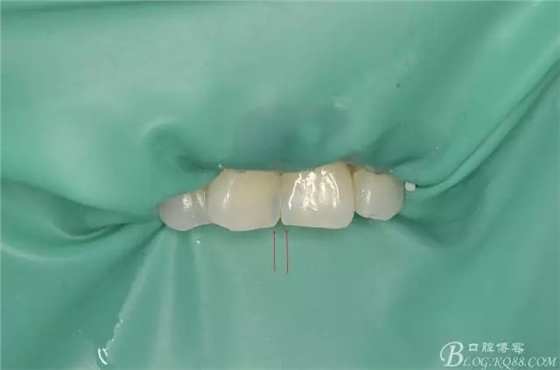

術(shù)后即刻:

(箭頭處所指,可見明顯脫礦發(fā)白!)

術(shù)后即刻照,發(fā)現(xiàn)兩中切牙近中切角區(qū)明顯發(fā)白??